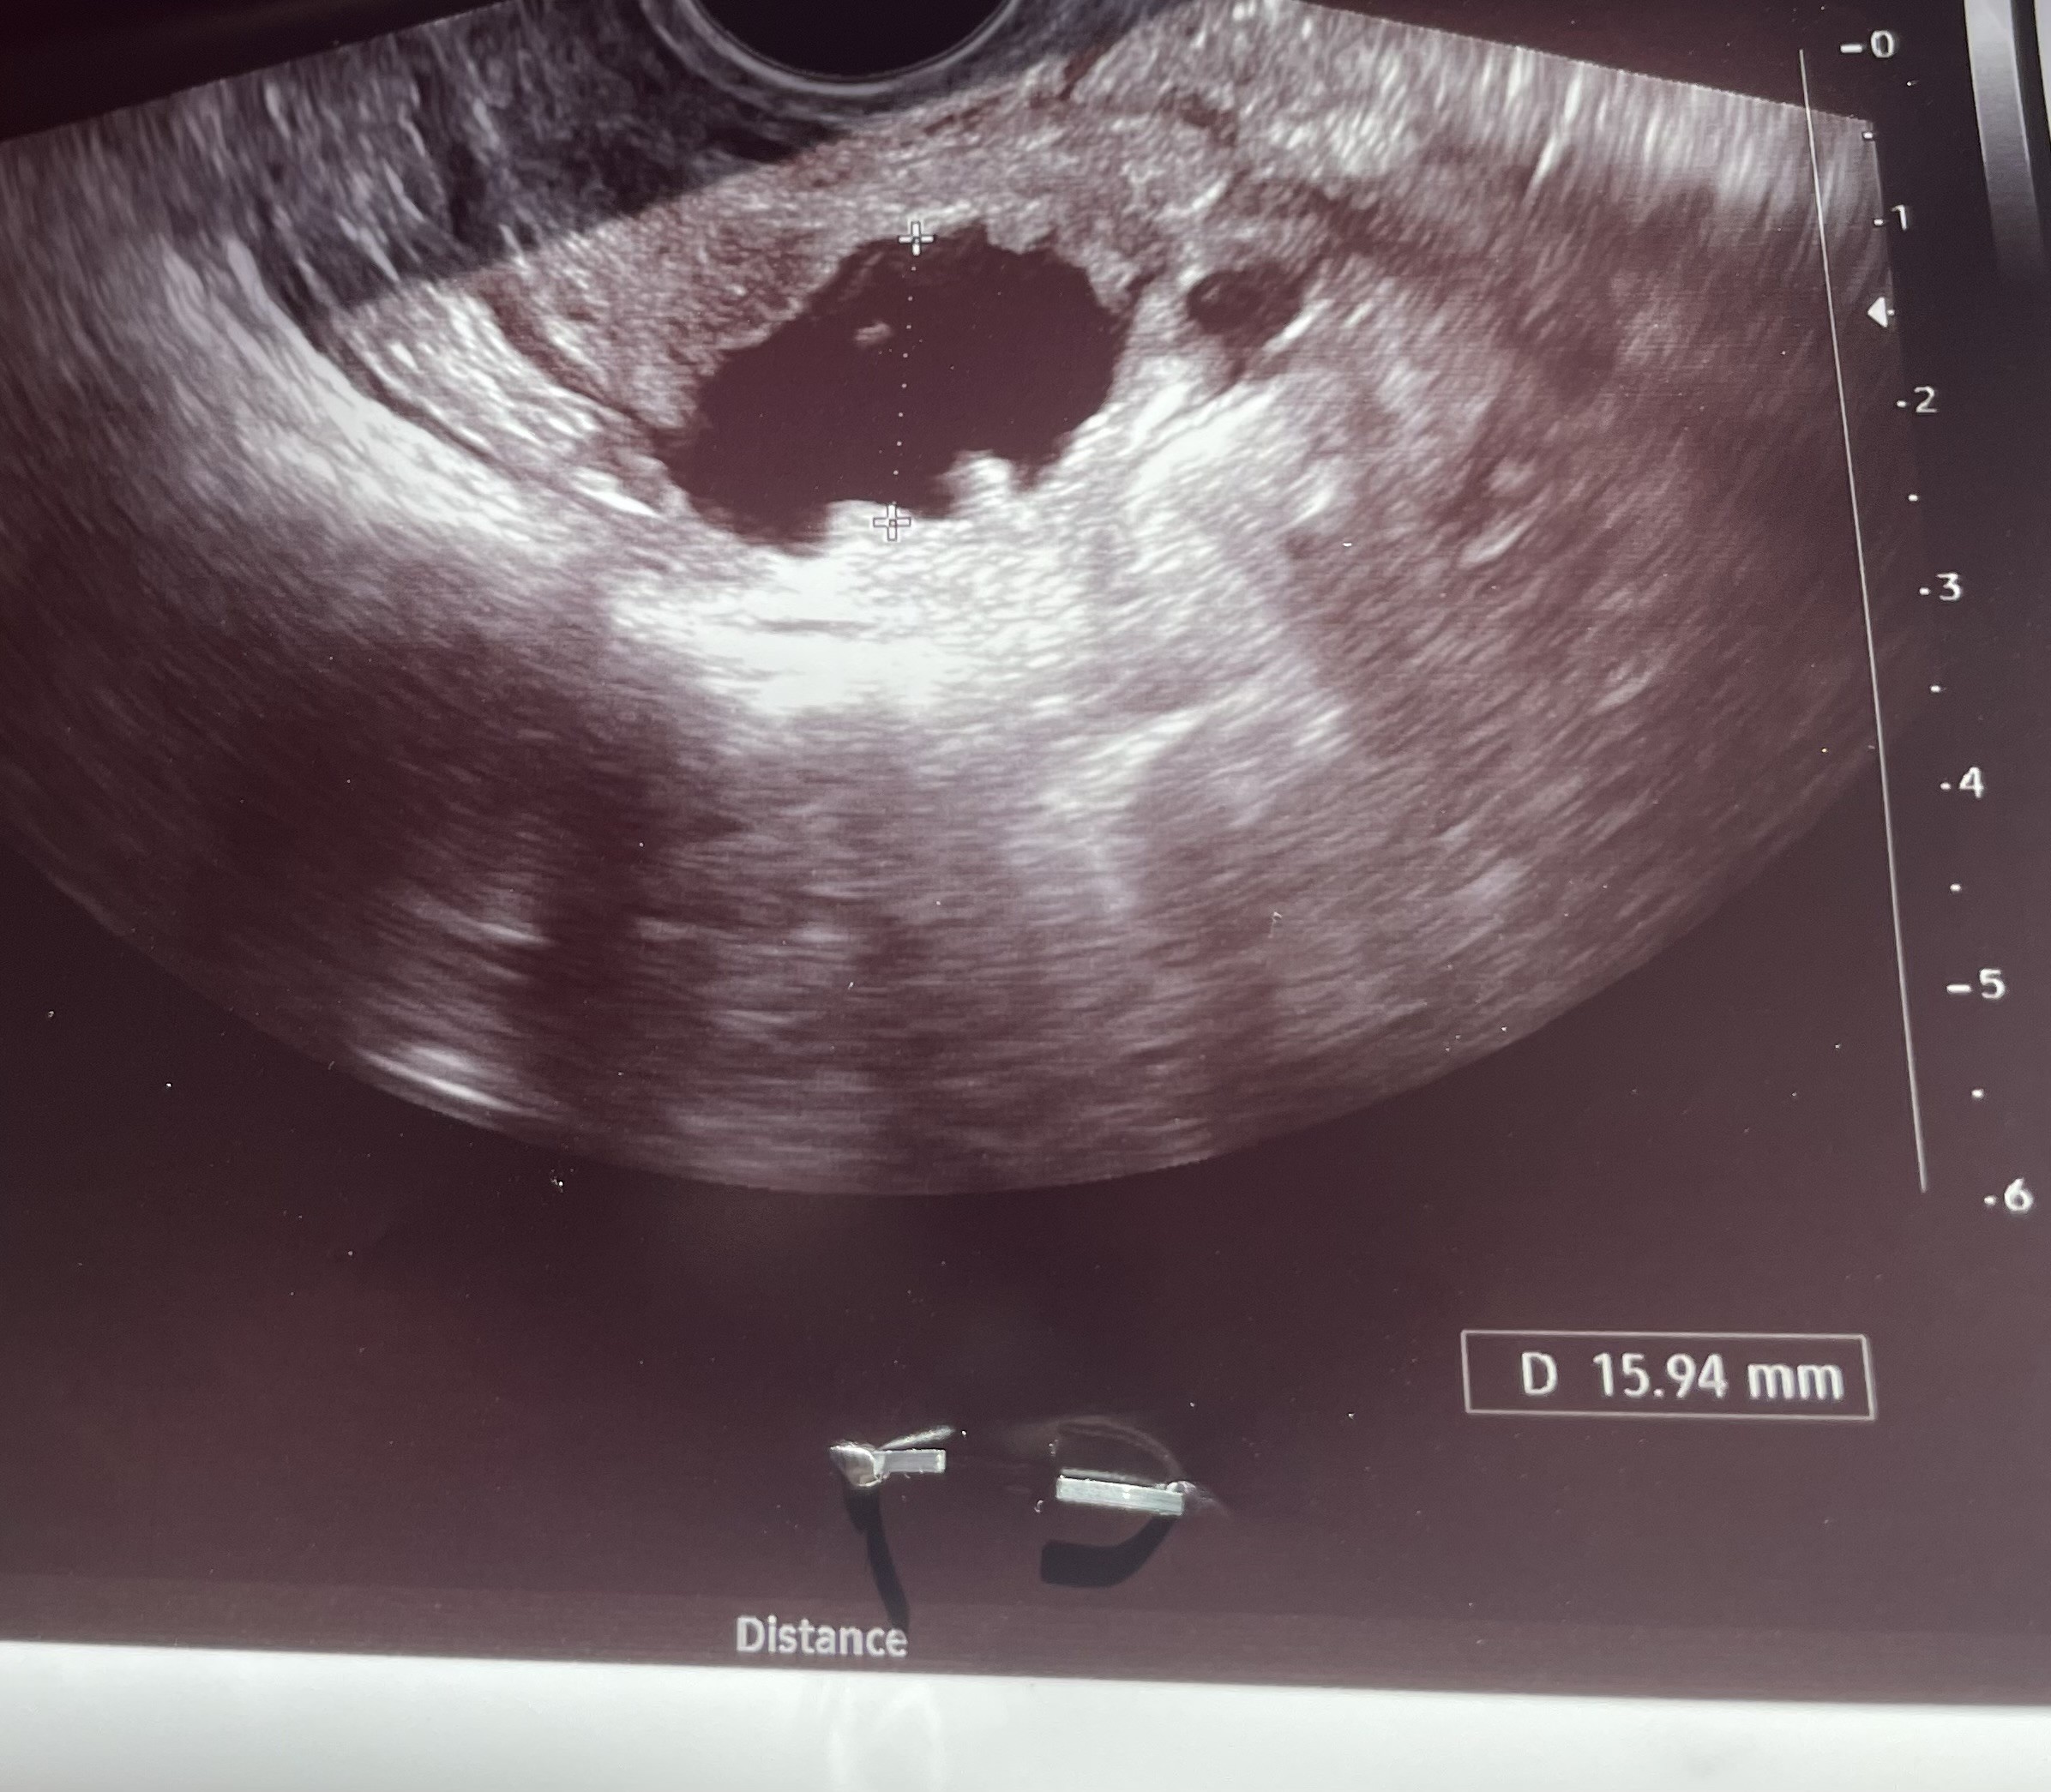

2 cykl stymulowany , poszłam dziś na usg 13 dc. A lekarz zobaczył pęcherzyk o nieregularnych kształtach o średnicy 15.9mm . To oznacza , że już po owulacji?

Pytałam powiedział , że nie jest w stanie mi odpowiedzieć kiedy pękł. Czyli jakbym dopiero dzisiaj planowała starania to już raczej bez szans w tym cyklu?Moim zdaniem to oznacza, że ten pęcherzyk jest po owulacji.

Nieregularny kształt to już po ptokach ale możesz dzis się starać bo on musiał dopiero pęknąć.